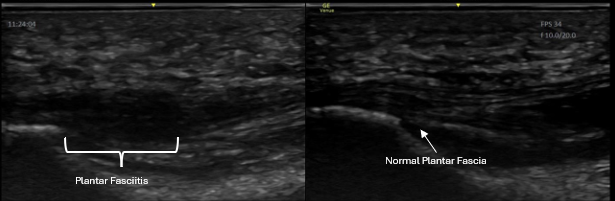

Not All Heel Pain Is the Same

Pain in the back or bottom of the heel may come from:

• Mid-substance Achilles tendinopathy

• Insertional Achilles tendinopathy

• Partial Achilles tears

• Retrocalcaneal bursitis

• Plantar fasciitis / plantar fasciopathy

• Partial plantar fascia tears

• Ankle joint or tendon pathology

• Scar tissue after previous sprains

Symptoms overlap. Without imaging, treatment often becomes generalized rather than targeted.

This is why we begin with diagnostic ultrasound.

Plantar Fascia Pathology

• Plantar fasciitis / fasciopathy

• Thickened or degenerative plantar fascia

• Heel spur-related irritation